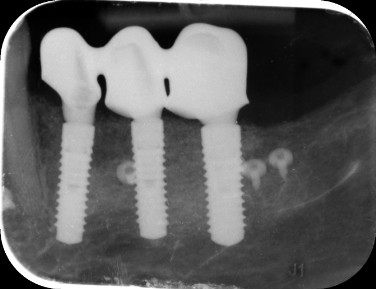

A sikeres gyógyulási időszak után elkészült a végleges, rögzített híd. Ez a lépés legalább olyan fontos, mint a műtét: itt válik a szájsebészeti alapozás egyedi, esztétikus, prémium fogpótlássá. A kezelés sikerét a kontroll röntgenfelvétel is tökéletesen igazolja: